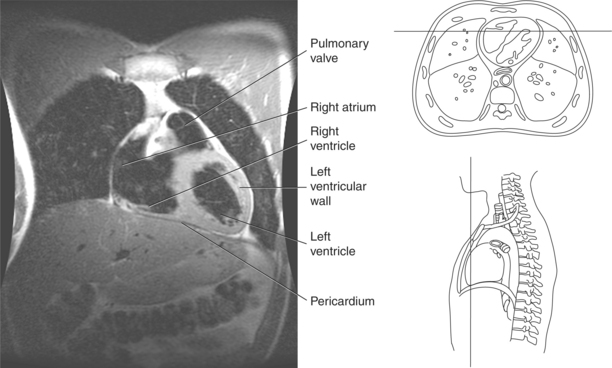

The heart is a hollow, four-chambered muscular organ located within the middle mediastinum. It is approximately the size of a large clenched fist and is situated obliquely in the chest with one third of its mass lying to the right of the median plane and two thirds to the left. The heart can be described as being roughly trapezoid shaped (Figure 6.33). The superficial relationships of the heart include the base, apex, three surfaces (sternocostal, diaphragmatic, pulmonary), and four borders (right, inferior, left, and superior). The broad base (posterior aspect) is the most superior and posterior portion of the heart. It is formed by both atria, primarily the left atrium, and gives rise to the great vessels. The apex is formed by the left ventricle and points inferiorly, anteriorly, and to the left. It is located at the level of the fifth intercostal space, just medial to the midclavicular line. The sternocostal (anterior surface) is formed primarily by the right atrium and right ventricle with a small contribution from the left ventricle. The diaphragmatic (inferior surface) rests on the central tendon of the diaphragm and is formed by both ventricles and a small portion of the right atrium. The pulmonary (left surface) is formed mainly by the left ventricle and fills the cardiac notch of the left lung. The borders of the heart represent the external surfaces of the cardiovascular silhouette in radiographic profile. The borders include the right border, formed by the right atrium and located between the superior and inferior venae cavae; the left border, formed by the apex of the heart or the left ventricle; the superior border, formed by the right and left atria; and the inferior border, which is formed primarily by the right ventricle with a small contribution from the left ventricle (Figures 6.33 through 6.35).

The heart is enclosed in a pericardial sac that surrounds the heart and the proximal portions of the great vessels entering and leaving the heart. The fibrous pericardium is attached to the central tendon of the diaphragm and is pierced by the inferior vena cava. The inner surface of the fibrous pericardium consists of a double-layered serous membrane termed the serous pericardium. The serous pericardial layers are the parietal layer that lines the inner surface of the fibrous pericardium and the visceral layer (epicardium) that covers the outer surface of the heart and the roots of the great vessels. Located between the two layers is a potential space (pericardial cavity) containing a thin film of serous fluid that acts as a lubricant to reduce friction to the tissues caused by heart movement. Located between the pericardium and the heart wall is a layer of epicardial fat that is typically more prominent near the venous inflow and arterial outflow of the heart (Figures 6.36 through 6.38).

The walls of the heart consist of three layers: (1) epicardium, the thin outer layer that is in contact with the pericardium; (2) myocardium, the thick middle layer consisting of strong cardiac muscle; and (3) endocardium, the thin, endothelial layer lining the inner surface. The endothelial layer also lines the valves of the heart and is continuous with the inner lining of the blood vessels. The heart is divided into four chambers: the right and left atria and the right and left ventricles. The two superior collecting chambers called atria are divided by the interatrial septum. During embryonic development an oval opening exists within the interatrial septum called the foramen ovale. This opening allows blood flow between the right and left atria during fetal lung development. At birth, the foramen ovale closes, leaving a small depression in the septal wall called the fossa ovalis in the adult heart. The two inferior pumping chambers called ventricles are divided by the interventricular septum (Figure 6.39).

The right atrium forms the right border of the heart and receives deoxygenated blood from the body via the superior and inferior venae cavae and from the coronary sinus and cardiac veins that drain the myocardium. A small muscular embryonic appendage, the right auricle, projects upward and toward the left from the right atrium, covering the root of the aorta (Figure 6.40). The right ventricle lies on the diaphragm and comprises the largest portion of the anterior surface of the heart. It receives deoxygenated blood from the right atrium and forces it into the pulmonary trunk for conveyance to the lungs. Projecting off the inferior surface of the ventricular walls are conical-shaped projections of cardiac muscle called papillary muscles that anchor the cusps of the tricuspid valve to the right ventricle (Figure 6.39). The left atrium lies posterior to the right atrium and is the most posterior surface of the heart. It also has an embryonic appendage, the left auricle, that projects to the left of the pulmonary trunk over the superior surface of the heart. The left atrium receives oxygenated blood directly from the lungs via the four pulmonary veins (two on each side). The left ventricle forms the apex, left border, and most of the inferior surface of the heart. It receives oxygenated blood from the left atrium and pumps it into the aorta for distribution throughout the systemic circuit. The myocardium of the left ventricle is normally three times thicker than that of the right ventricle, reflecting the force necessary to pump blood to the distant sites of the systemic circulation (Figures 6.41 through 6.52). Two papillary muscles project from the ventricular walls to anchor the bicuspid valve to the ventricle (Figures 6.39 and 6.47).

Figure 6.43 Axial, T1-weighted MR scan of left atrium.

Key: RV, Right ventricle; LV, left ventricle; LA, left atrium; RA, right atrium.